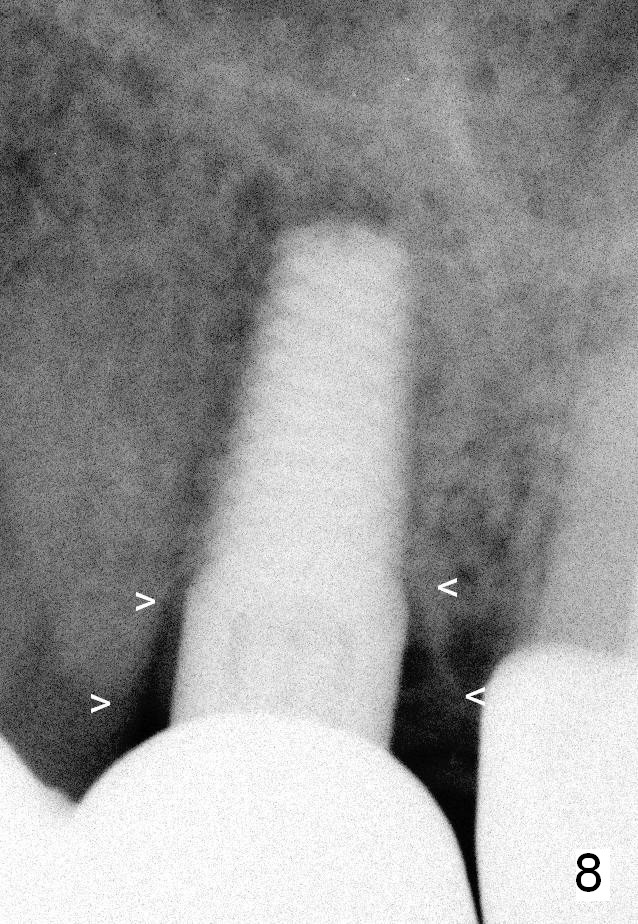

A 45-year-old lady is nervous about dental treatment. The missing tooth #13 was replaced by a 3-unit bridge. The latter is sectioned because the posterior abutment has caries. PA in Fig.1 is taken when root canal therapy and build up are finished. Fig.2 shows the wide edentulous area with a single-unit crown being tried in for #14. Osteotomy is initiated with the crown in place without cementation, since it is easy to determine the mesiodistal position (Fig.3 red lines). Without the crown in place, osteotomy tends to be distal. In this case, the osteotomy is later attempted to be moved distally with Lindamann bur and deepened to 14 mm from the gingival margin (Fig.4). A 2.5 mm reamer is being used at 50 RPM to increase osteotomy with difficulty. Drills have to used at high RPM instead (Fig.5 4x14 mm). A 4.5x14 mm tissue-level implant is placed with insertion torque >60 Ncm (Fig.6 I); a 4x3 mm abutment (A) is placed immediately for an immediate provisional. Fig.7 is taken 7 days postop to show the gingival recipient site formed by the provisional. The patient is so afraid of X-ray that the next one is taken 1.5 years post cementation (Fig.8). It appears that dense bone bundle forms between the crest and the 1st implant thread (adaptation functional change, arrowheads). The bone density continues to increase 2 years 8 months post cementation (Fig.9 *, 10); the bone has grown into the area between the 1st 2 threads (arrow).